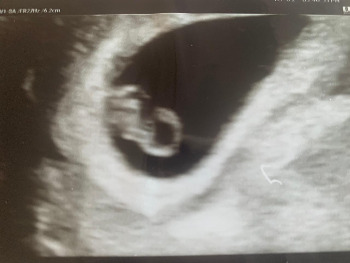

처음 만난 너는 작은 동그라미에 불과했다.

사람이라기보다는 포도송이 같았던 너를 보고, 한눈에 사랑에 빠지기는 어려웠다.

짧은 시간 동안 몰라보게 자란 너는 젤리곰의 모양을 하고 있었다.

짧은 팔과 다리를 움직거리는 너의 모습을 보았을 때,

나는 순간적으로 차오르는 사랑에 짐짓 황홀함마저 느끼고 말았다.